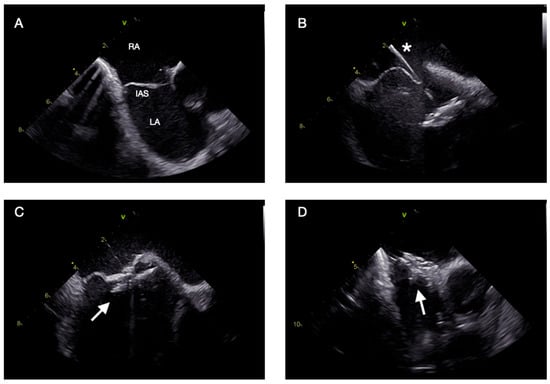

Intracardiac Echocardiography in Structural Heart Interventions: A Comprehensive Overview

by Francesco Leuzzi, Ciro Formisano, Enrico Cerrato, Antongiulio Maione, Tiziana Attisano, Francesco Meucci, Michele Ciccarelli, Carmine Vecchione, Gennaro Galasso and Francesca Maria Di Muro

Intracardiac echocardiography (ICE) is increasingly recognized as a valuable imaging modality in structural heart interventions, offering high-resolution, real-time visualization from within the cardiac chambers. Originally developed for electrophysiologic procedures, ICE has expanded its use across a broad spectrum of structural interventions, including atrial [...] Read more.

Intracardiac echocardiography (ICE) is increasingly recognized as a valuable imaging modality in structural heart interventions, offering high-resolution, real-time visualization from within the cardiac chambers. Originally developed for electrophysiologic procedures, ICE has expanded its use across a broad spectrum of structural interventions, including atrial septal defect (ASD) and patent foramen ovale (PFO) closure, left atrial appendage occlusion (LAAO), transseptal puncture guidance, transcatheter edge-to-edge repair (TEER), balloon mitral valvuloplasty, and both mitral and tricuspid valve therapies. This review outlines the current role and technical principles of ICE, with an emphasis on catheter design, image acquisition protocols, and the emerging potential of 3D ICE. Comparisons with transesophageal echocardiography (TEE) and fluoroscopy are discussed, highlighting ICE’s ability to support minimally invasive, sedation-sparing procedures while maintaining procedural precision. We provide a focused analysis of ICE-guided applications in specific clinical scenarios, emphasizing its role in anatomical assessment, device navigation, and intra-procedural monitoring. Data from recent clinical studies and registries are reviewed to assess safety, feasibility, and outcomes. Practical considerations including operator learning curve, workflow integration, and limitations such as cost and field of view are also addressed. Lastly, we explore future directions including advanced 3D imaging, fusion imaging, artificial intelligence integration, and robotic catheter systems. Full article